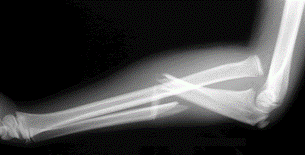

What fracture is this?

Monteggia fracture

Proximal ulna fracture

Radial head dislocation